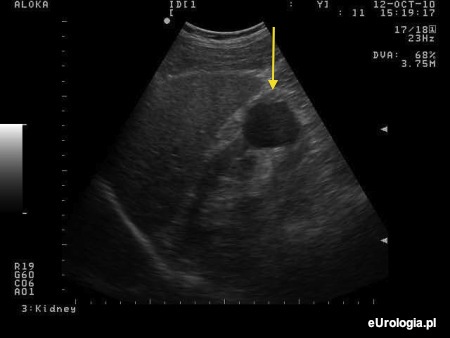

Domyślamy się, że określenia cysta używa Pan mając na myśli torbiel prostą nerki. Torbiel prosta jest cienkościenną przestrzenią wypełnioną płynem. Torbiel o takich rozmiarach i lokalizacji nie wymaga dodatkowej diagnostyki i leczenia. Więcej informacji znajdzie Pan w artykule: Torbiele proste nerek.

Fot. Torbiel prosta dolnego bieguna prawej nerki.